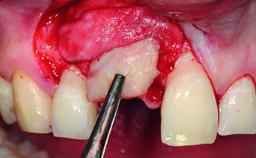

A 32-year-old female Caucasian patient with a compromised maxillary right central incisor was referred to us by a general dentist. Her chief complaints were discomfort and mobility of tooth 11 with unsatisfactory esthetics due to discoloration. The patient reported a previous trauma, some years earlier, as the origin of pathology on the afflicted tooth. Anamnesis was negative for any other dental or periodontal pathology in the remaining dentition. The patient did not take any medication and reported to be a light smoker (5–10 cigs/day). She had high esthetic expectations of her treatment. The extraoral examination revealed a high smile line with full exposure of her maxillary teeth and surrounding soft tissue in the area between the second premolars.

Bone Augmentation Horizontal|Simultaneous|Staged

Augmentation Materials Autogenous chips|Xenogenous|Membrane

Bone Volume Horizontally and vertically sufficient Horizontally deficient Deficient vertically or deficient vertically AND horizontally

Bone Volume Deficient horizontally, requiring prior grafting